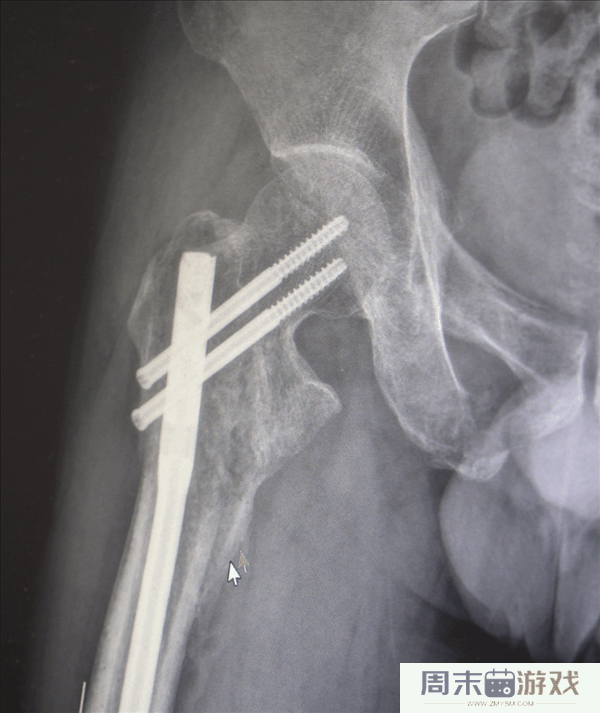

创伤性失血性休克、多发性肋骨骨折、肺部损伤、右侧肩胛骨粉碎骨折、右侧肱骨髁上开放粉碎性骨折、右股骨粗隆及股骨干粉碎性骨折、骨盆粉碎性骨折、腰椎横突多发骨折、腰骶柱神经损伤、臂丛神经损伤、胸腔积液、腹腔积液等。

经医生检查,张先生全身共有六处较大骨折部位,多为严重粉碎性骨折,全身骨折碎块达30多块!

鉴于男子多处骨折,其中最严重的当属右肘部C3型粉碎性骨折,关节面及髁上严重粉碎(碎成了七块),肘关节易粘连,复位固定难度极高。